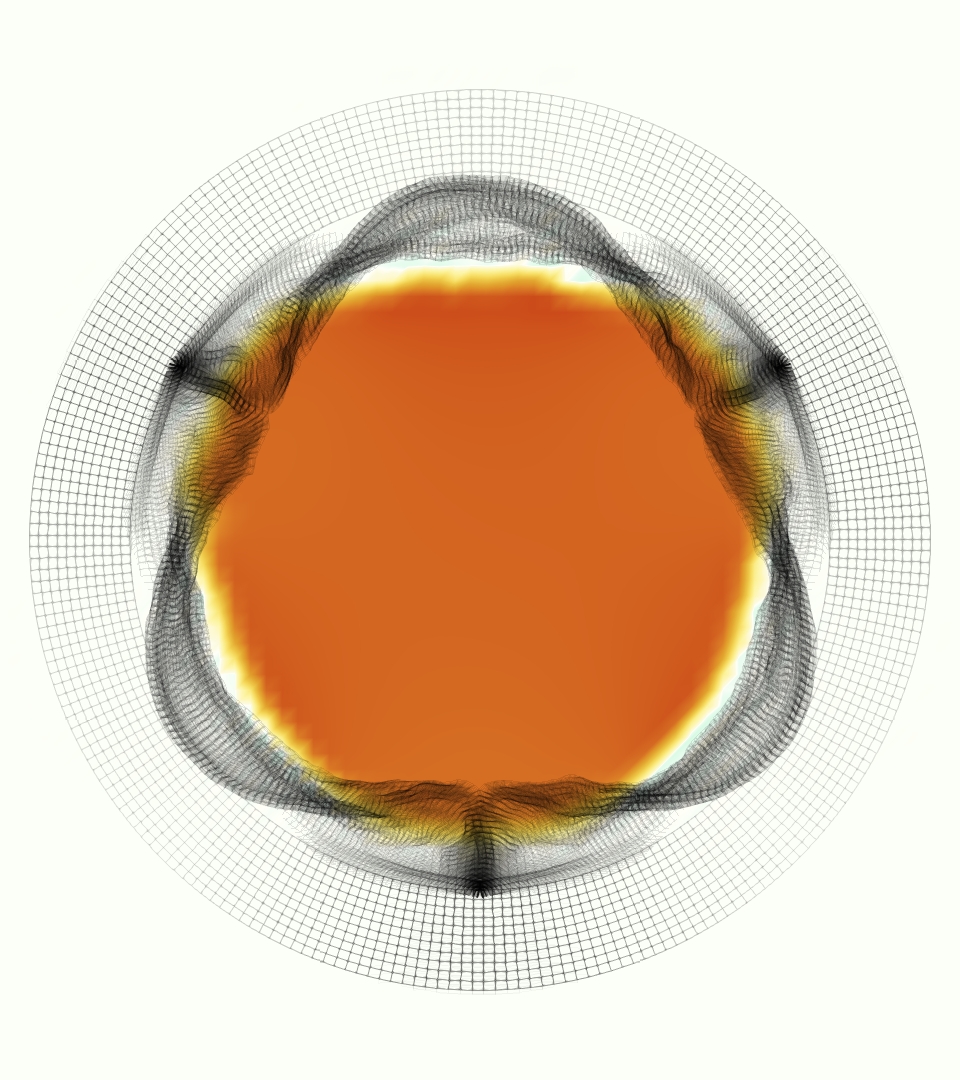

The gross morphology of the model valve that emerged from this process is shown in Figure 4. The free edge was 2.87 cm, corresponding to 3.3 cm in the predicted loaded configuration. After the pinching the leaflets together at the commissures, this left approximately 2.1 cm of free edge rest length per leaflet free to move independently of the other leaflets, within measurement error of ±0.1 cm from the free edge length of 2.2 cm measured on the prostheses. The leaflet rest height was 0.94 cm corresponding to a predicted loaded height of 1.44 cm. The measured leaflet height of 1.3 cm is nearly the predicted loaded height of 1.44 cm, which may be because the leaflets are so compliant in the radial direction, that pulling them flat to measure them achieved substantial stretches. The fiber orientation of the model runs from commissure to commissure and qualitatively matches experimental observations [38], though direct quantitative comparison is beyond the scope of this work. One minor limitation is that we do not add bending rigidity to the leaflets, beyond what emerges from the thickening process described above, and thus may not accurately capture leaflet flutter or other similar behaviors. Based on the thickness of mm, we estimated the mean tangent modulus at the predicted loaded stretches as dynes/cm2 circumferentially and dynes/cm2 radially. The prosthetic valve tissue is fixed in glutaraldehyde, and literature values for the fully-recruited circumferential tangent modulus of fixed porcine aortic valve tissue vary widely. Based on the experimental measurements of Billiar and Sacks and their constitutive law for valves fixed under 4 mmHg of pressure, we evaluated their constitutive law at the relevant stretches and and estimated the circumferential tangent modulus to be dynes/cm2 [6]. Rousseau et al. reported moduli ranging from to dynes/cm2, depending on the applied preload during fixation [36]. Sung et al. reported moduli ranging from to dynes/cm2, depending on fixation pressure [43]. Thus our estimated tangent modulus falls within the range of existing studies, so we considered our resultant modulus in good agreement given the complexity of the steps involved, phenomenological nature of the constitutive law and uncertainties in experiments. We do not have access to the precise material properties of the prosthetic valve, and further, the only literature we could find on the material properties of a similar prostheses reported the tangent modulus at one particular loading, which did not appear to be at a relevant stretch for comparisons with our model [19]. Thus, our model has material properties in a reasonable range for a fixed aortic valve prostheses (placed in the pulmonary position in our simulations), but it does not directly model the material properties of the prostheses.

We constructed the model vessel for FSI simulations from data from the MRI scans (Figure 4). The signal magnitude of 3D printed model material is distinct from the signal of the fluid in the scans, and we applied a thresholding operation to generate a three-dimensional model of the printed vessel surface. Using the MRI data ensured that the MRI and simulation coordinates were consistent in space and there were no alignment or registration errors. While using the files that generated the 3D printed model would have offered more spatial fidelity, the potential error in flow fields due to any mis-registration would have likely been much more substantial. Using Meshmixer (San Rafael, CA), we smoothed the mesh to remove stair-step effects and removed artifacts from the valve scaffold. We then remeshed to the desired edge length of 0.25 mm and extruded the model 0.25 mm and 0.5 mm to create a three-layer structure. As in the valve, this serves to eliminate the “grid aligned artifact” that can occur with pressure differences across thin membranes in the IB method [16]. Flow extenders of length 1 cm were added to the vessel at the inlet and both outlets to ensure that the normal to the vessel was aligned with the normal of the fluid box at the inlets and outlets. In FSI simulations, the vessel was held in place using target points, stiff springs of zero rest length that connect the current position of each model node to its desired position (Section 3.3). Additional linear springs are placed on each edge in the triangulated model. These springs are not meant to model a particular material and only serve to keep the vessel rigid and stationary throughout the simulation.

At = 0, the axial slice directly at the valve annulus shown in columns 1 and 2 in Figure 6, there was excellent agreement between the simulation and experiment over the cardiac cycle in the speed and shape of the jet through the valve. In both cases, the axial velocity increased as the flow accelerated during systole and the valve leaflets opened, then decreased during diastole with slight negative velocity before the valve leaflets were fully closed. The forward flow through the valve annulus did not form a full circle, but rather developed a triangular shape with a point of the triangle forming along the interior curve of the vessel, at the bottom of the axial slices. At = 0, the points of this triangular jet shape aligned with the commissures of the valve. This shape persisted during peak systole and was well-matched by the simulation.

The axial slice = 0.625 cm, shown in columns 3 and 4 in Figure 6, cut through the support scaffolding of the valve and the leaflets when they are open. In the experimental data, the shape of the jet changed as it moved downstream. A triangular shape occurred, but the points were then aligned with the middle of each open leaflet as opposed to the commissures. Those points were also more rounded than they were at = 0. The peak velocity of the jet was faster at = 0.625 cm than at = 0, as the flow accelerated through the open valve leaflets. The simulation produced these features at = 0.625 cm. The triangular shape of the jet shifted similarly, and its speed increased compared to the upstream slice. As the flow decelerated into diastole, the jet shape remained roughly triangular but diminished in intensity before disappearing after valve closure.

The jet continued to develop at = 1.25 cm, an axial slice immediately downstream of the valve scaffolding and open leaflets, shown in columns 5 and 6 in Figure 6. In the experimental data, the points of the triangular jet shape extended further towards the vessel wall. In addition, regions of reversed flow developed in the locations downstream of the commissures, resulting in curved sides to the shape of the jet. Each tip of the jet was unique, due to variations in the individual leaflets in the physical bioprosthetic valve. These variations are apparent in the velocity fields, possibly because the jet edges are similar enough cycle to cycle that irregularities are still being captured even with phase averaging. Further discussion of these features can be found in Schiavone et al. [39], which showed that the jet tip shapes occurred in different pulmonary anatomies, demonstrating that they were likely due to inherent properties of each leaflet. The leaflets in the mathematical model of the valve are identical, so these nuances in leaflet variation could not be replicated. The simulation did capture some of the extension of the tips of the jet, as they were closer to vessel wall at slice = 1.25 cm than = 0.625 cm. The curves in the triangular sides of the jet were also present in the simulation, though they were less pronounced than the experimental data. At both = 0.625 cm and = 1.25 cm, the jet shape in the simulation was smoother than the jet in experiment. It is possible that the free edges of the leaflets in the mathematical model are not fully replicating the behavior of the physical leaflets of the bioprosthetic valve, in particular the amplitude or frequency of leaflet flutter, leading to the variations seen in the jet shape at = 1.25 cm downstream of the leaflet edges. The simulation, however, does capture the key features of the triangular shape and speed of the jet. Overall, qualitative comparisons demonstrated that the simulation reproduced key features of the flow during systole and diastole.

The phase-averaged, resampled velocity fields during peak systole and flow rates at each resolution are shown in Figure 10. Despite the limitations discussed above, we observe similar qualitative trends in the flow field at all resolutions. At all resolutions, a jet formed and angled up downstream of the valve orifice, as shown in the sagittal view. The jets showed a triangle-like cross section at with points aligned with the commissures. At cm, the jet appears like a rounded triangle in the opposing orientation, with its points aligned with the center of the leaflets. At cm, the jet is narrower downstream of the commissures, and wider downstream of the leaflets, again with a triangle-like cross section. The area of the jet increased with resolution, as expected given the IB method thickening of the valve structure. The narrowed jets at the two more coarse resolutions show locally elevated velocities relative to the two more fine resolutions. Figure 11 shows the instantaneous velocity fields at each resolution in the same axial and sagittal views. At 0.9 mm, the sagittal view shows a qualitatively different jet than at finer resolutions, with regions of lower velocity farther from the vessel wall, indicating insufficient resolution. At 0.9 and 0.68 mm, the jet is visibly narrowed compared to higher resolutions. While some features are similar at these two coarse resolutions, we conclude that the narrower jets indicate these simulations are under-resolved. Flows in the three finest resolutions, 0.45, 0.34 and 0.28 mm. appeared qualitatively similar, with slightly more fine structure detail in both the axial and sagittal views present at the edges of the jet. The jets in the axial views all showed a similar triangle-like cross section, slightly narrower downstream of the commissures, as in the phase-averaged fields. In both the phase-averaged and instantaneous fields, the three finest resolutions appear sufficiently similar that the conclusions of this study would be identical with any of these resolutions.